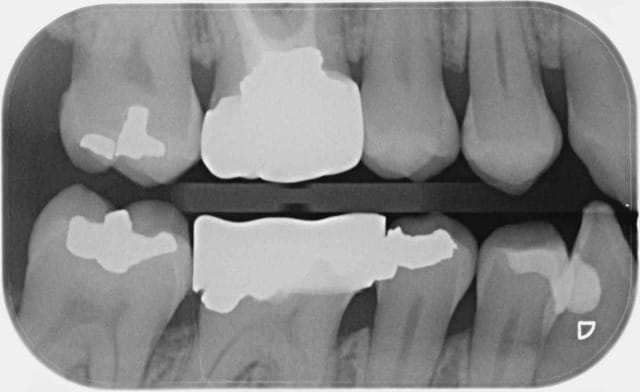

Ce message n'apporte rien au débat, c'est juste pour parler de cette patiente qui n'avait pas donné suite au devis pour couronner la 46. Au contrôle annuel suivant, la dent était couronnée, tout allait bien. Il a fallu que je lui pose la question pour qu'elle m'explique, sans la moindre gêne, que sa mutuelle GROUPAMA l'avait orientée vers un dentiste partenaire "moins cher".

Rien que sur la radio, je vous laisse admirer la qualité de la morphologie occlusale, le profil d'émergence, les points de contact (ou leur absence)... Je n'ai pas osé prendre de photo de ce blockhaus.

Bref, un an après, voici que la patiente revient pour me dire que la couronne ne va pas du tout, que ça la gêne.

Je me suis donc fait un malin plaisir de la renvoyer vers ce con-frère,

ET CA FAIT DU BIENNNNNNNNNNNNNN.